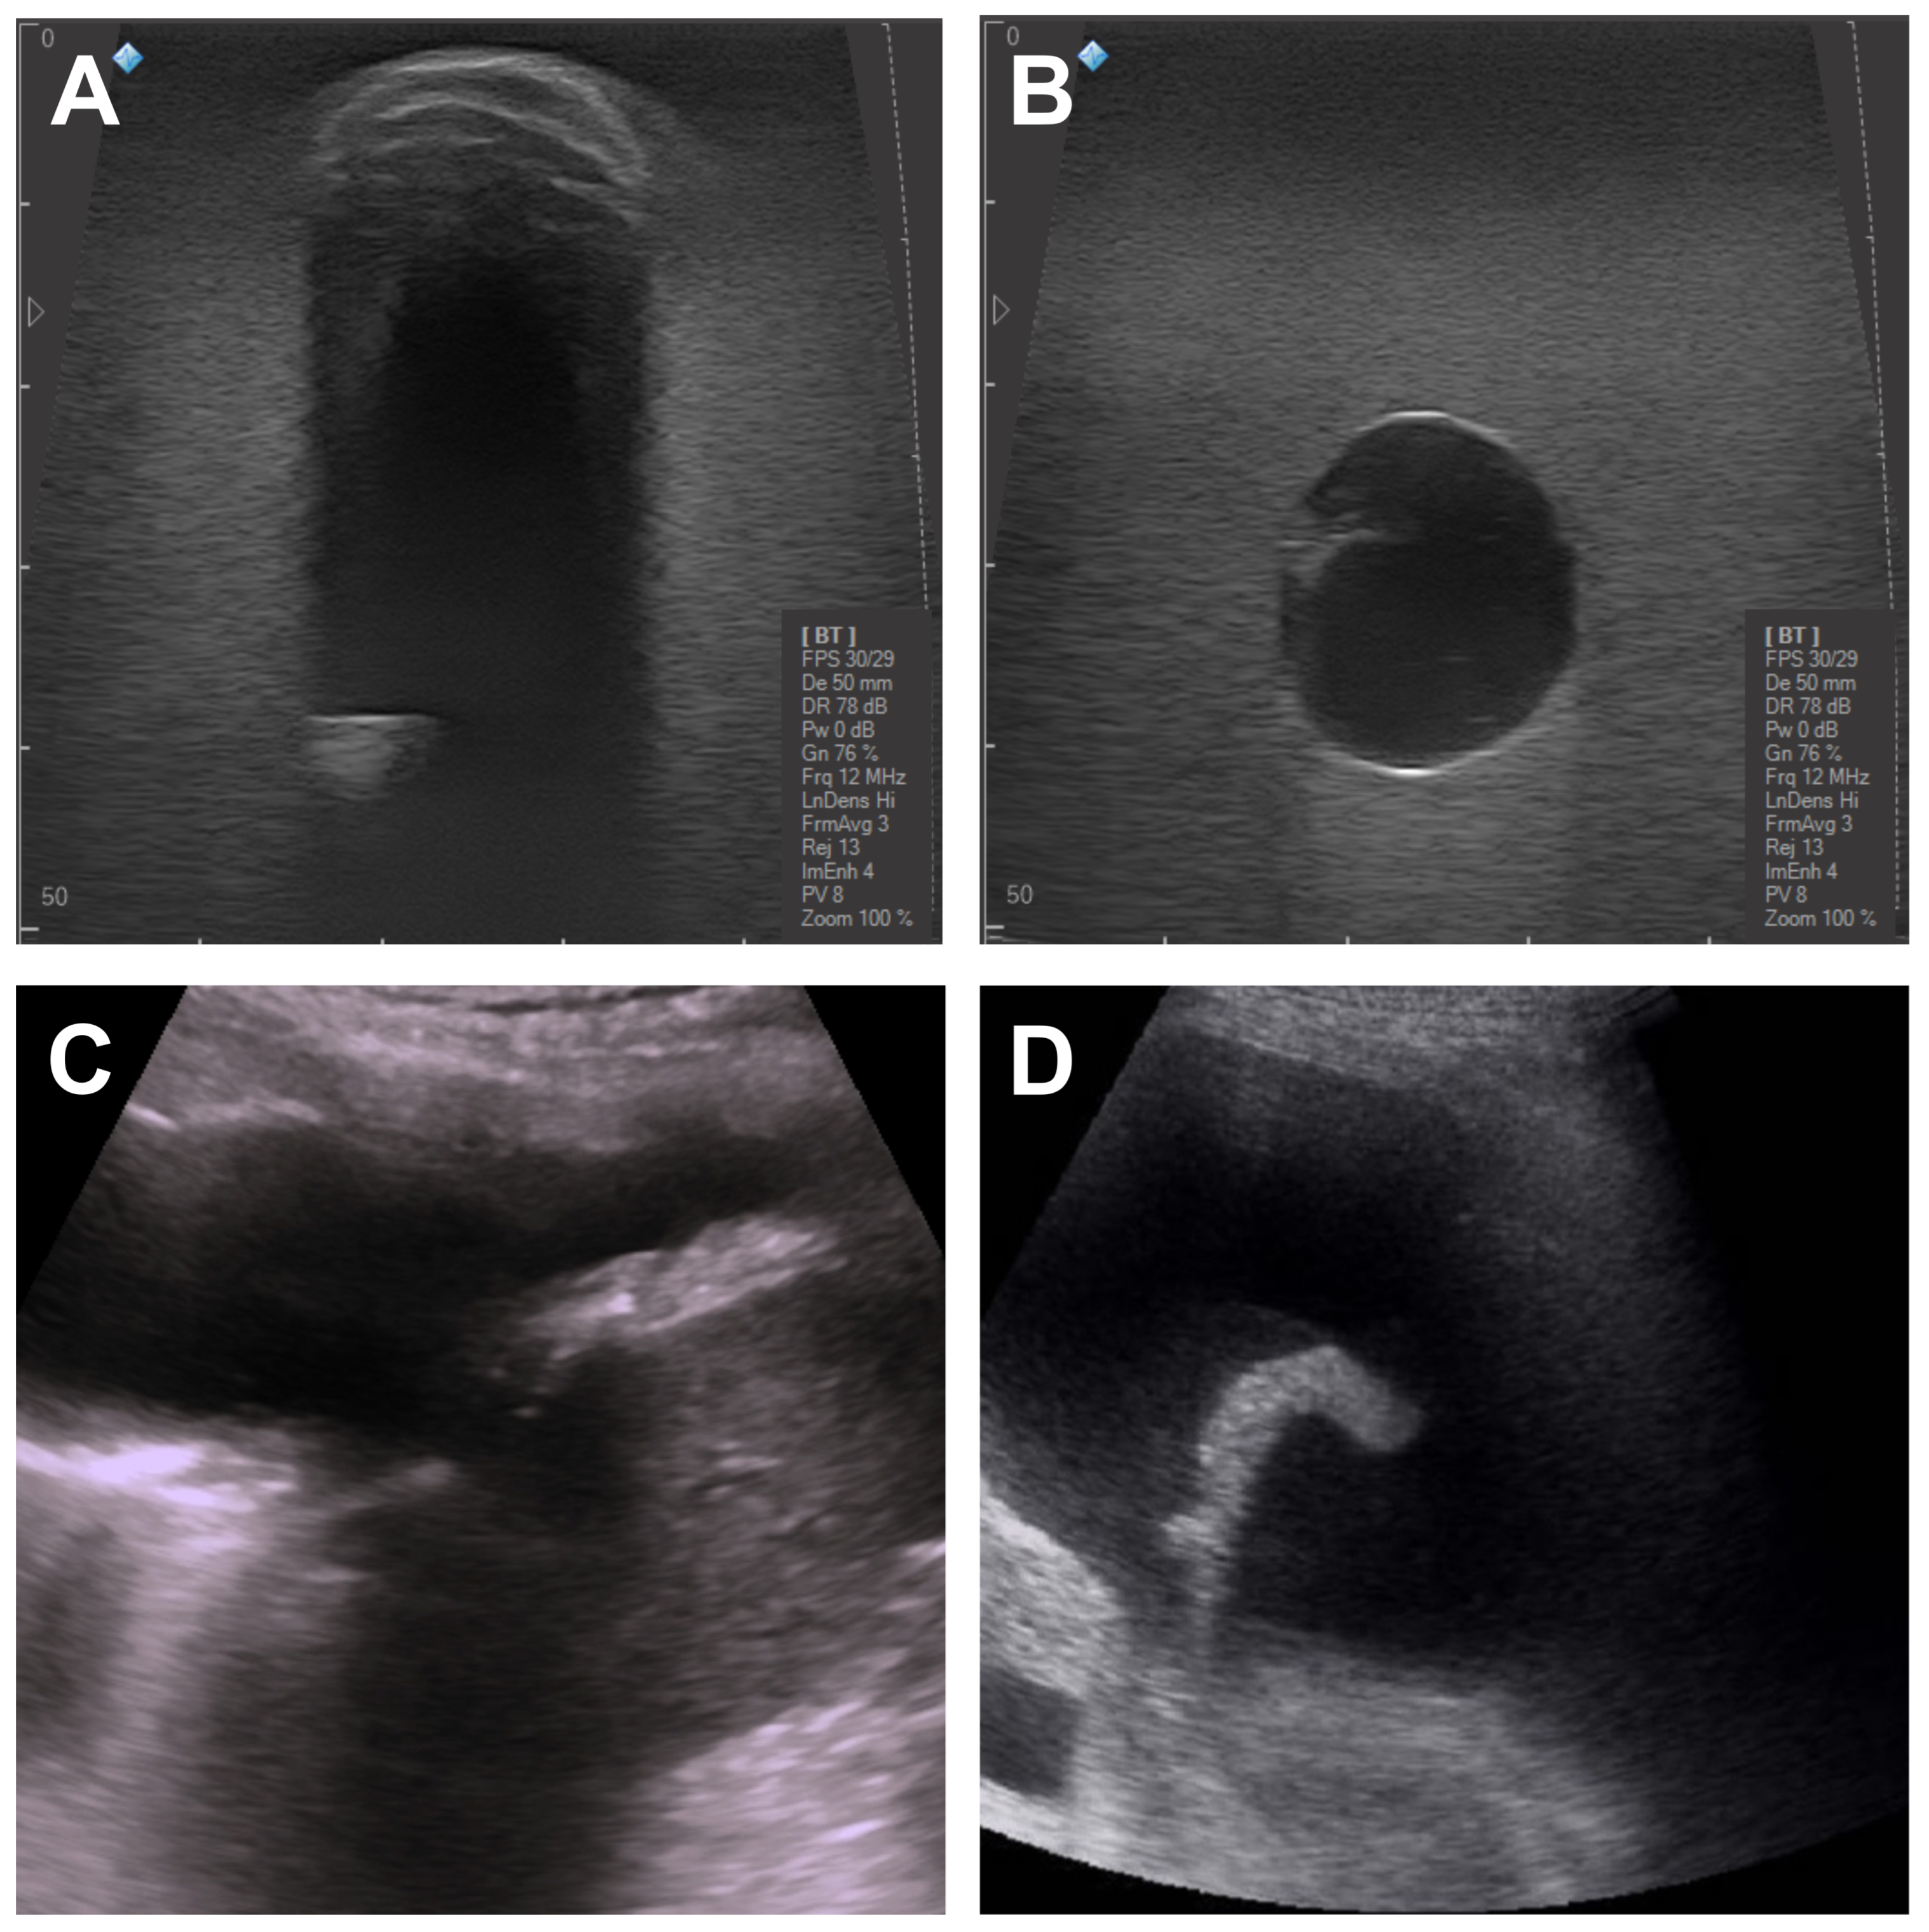

3.3. Invasive Surgical Procedures